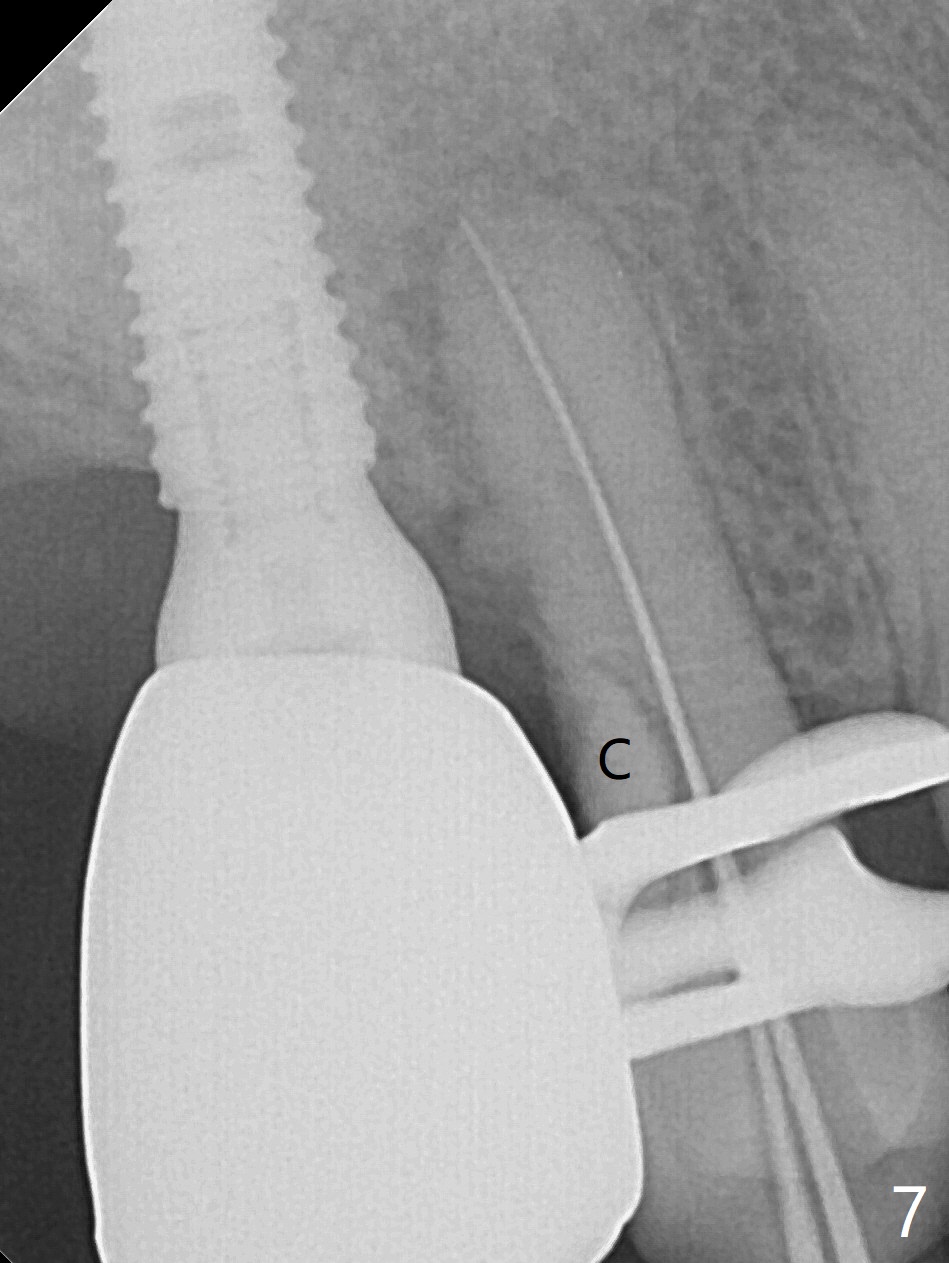

Bone Expansion Alternates with Drill

Since the ridge crest at #3 is narrow, Tatum bone scalpels are used to get access and initiate bone expansion, followed by bone blades and RT 2.  It seems that the osteotomy starts mesially; bone height being increased (Fig.1).  When the apical end of the osteotomy tilts mesially, more bone height is obtained.  Drills are alternatively applied because of the hard bone (Fig.2).  A 4x13 mm UF implant is placed initially with the distal threads unburied (Fig.3, >50 Ncm).  With further seating of the implant, a 5.5x5(4) mm abutment is used (Fig.4), which closes the access.  No suture is warranted.  An immediate provisional is fabricated for the patient's comfort and psychological effect.  In fact, the abutment cuff changes to 5 mm prior to temporarization.  There appears no bone loss <4 months postop (Fig.5).  Pulpitis develops at #4 due to DO caries 1 year 5 months post cementation (Fig.6 *).  The crown at #3 is removed for easy and conservative distal carious removal and Cavit temporary restoration to prevent sodium hypochlorite leakage.  Then occlusal access is made for pulpotomy.  When RCT finishes, no crown will be made, but occlusal reduction is required.    The patient returns for RCT 1 month later (Fig.7,8). Cavit remains in place (Fig.7 C).  Although 2 threads are exposed distal (Fig.8 arrow), there is no sign or symptom of periimplantitis, which may be related to the thick gingiva (arrowhead).  Return to Upper Molar Immediate Implant, IBS, #14 (Tissue Punch) Xin Wei, DDS, PhD, MS 1st edition 08/25/2017, last revision 09/08/2019